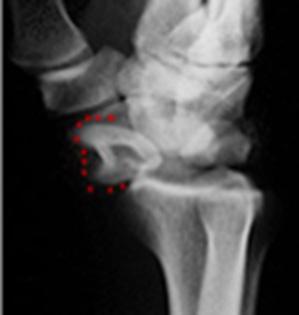

Luxofracturas

Luxofractura de Bennet: es una fractura oblicua de la base del primer metatarsiano que genera un desplazamiento cefálico del pulgar. (Ver Figura 62)